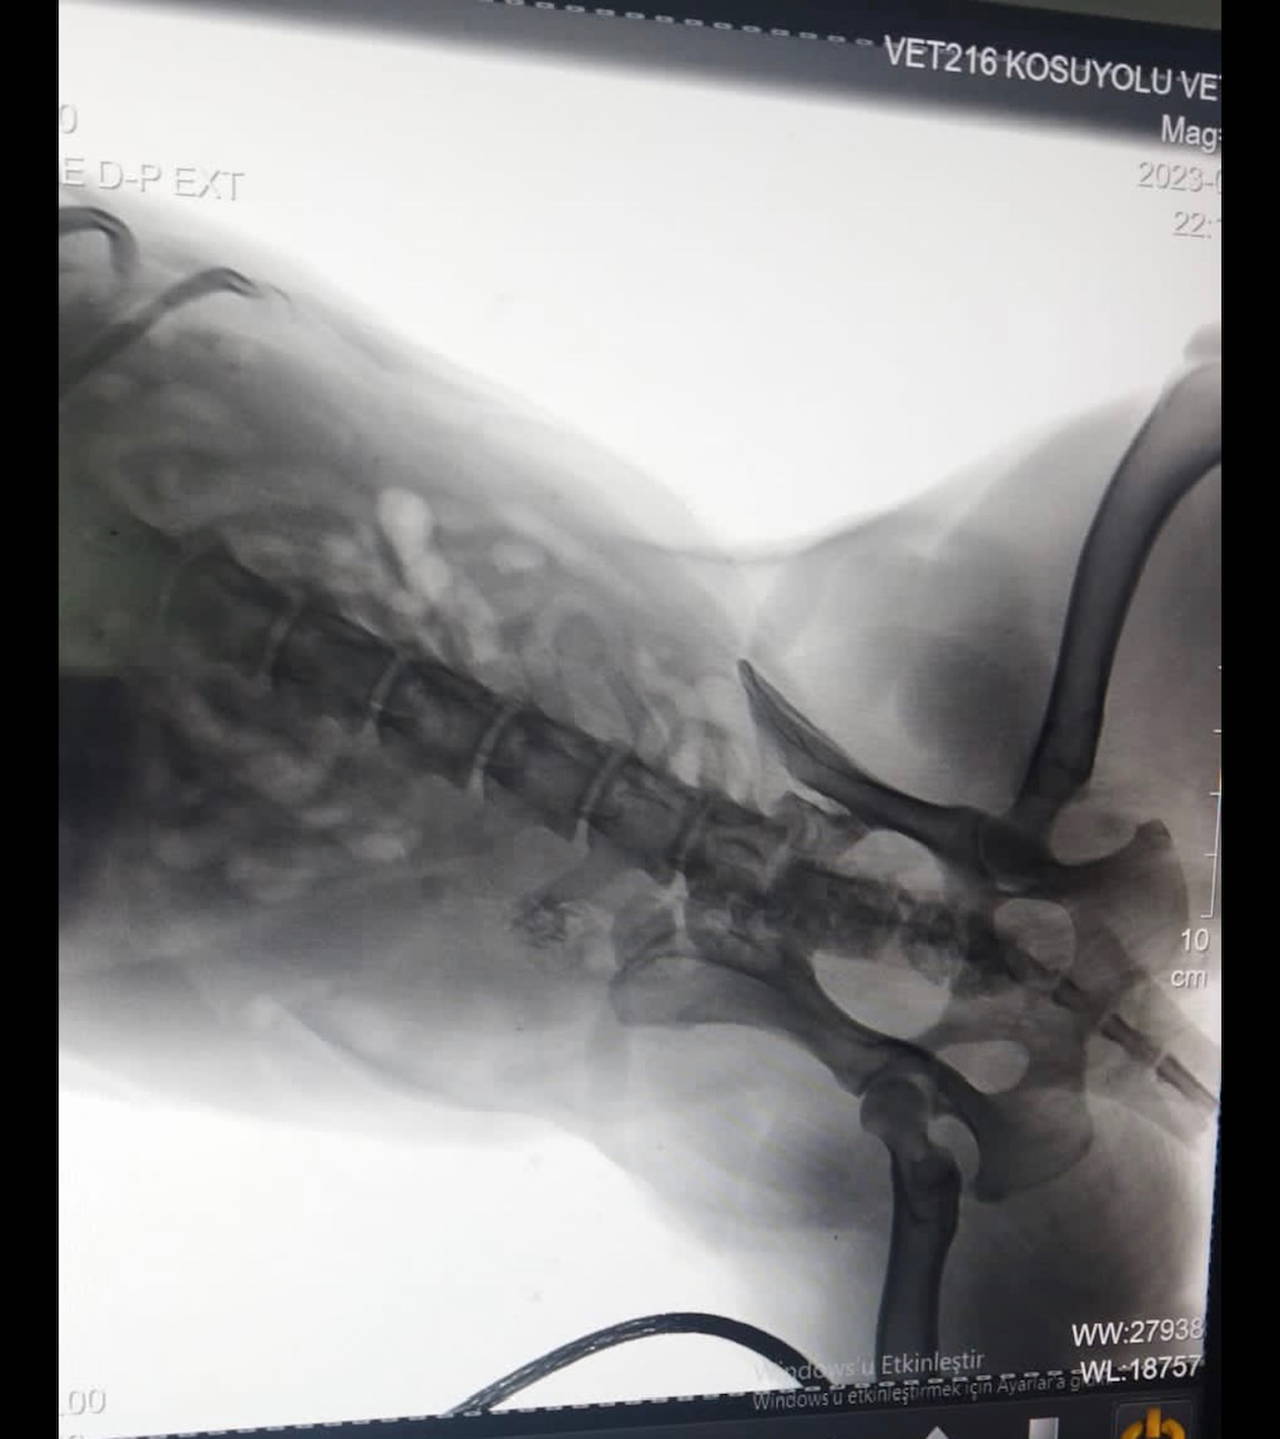

OMURİLİĞİNE İSABET ETTİ

Kurşunun köpeğin omuriliğine isabet ettiği belirlendi. Köpeğin sağlık durumunun ciddiyetini koruduğu öğrenilirken, mahalle sakinleri polise giderek şikayetçi oldu.

Mahalle sakini Ela Durmazer ise, "Bu olay gerçekten çok üzücü. Bunun gibi birçok vaka var. Hayvan çok kötüydü. Omuriliğine saplanmış bir kurşun var. Şu an hayvan ameliyata da alınamıyor çünkü çok riskli bir ameliyat. Vücudunun güçlendirilmesi için mücadele ediyoruz. Bizim amacımız böyle şeylerin yapılmaması. Hiçbir koşulda hiçbir canlıya silahla ateş edilmemesi gerektiğini artık lütfen herkes duysun. Hiçbir canlıya bu yapılmayacak. Ve yapılmaması için tutanağı ben tutturdum. En azından hukuki sürecin başında olacağız" diye konuştu.